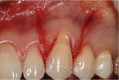

Gingival recession is an oral health problem that affects a large part of the population. Several treatments are suggested in the current literature; among them is the use of buccal fat pad grafting. The objective of this case report is to describe the treatment of a Miller Class I gingival recession using a nonpedicled buccal fat pad graft immediately after performing the surgery for buccal fat pad removal (bichectomy technique). First, bilateral surgical removal of the buccal fat pad was performed with the main objective of eliminating oral mucosa biting. The recipient site was prepared to receive a portion of the fat pad that was cut and macerated in a size that was sufficient to cover the recession. The patient was followed up at 15, 30, 60, and 365 days postsurgery, and the results showed an elimination of the oral mucosa biting and complete coverage of the gingival recession. It was concluded that the nonpedicled buccal fat pad graft is another option for the treatment of Miller Class I recessions.